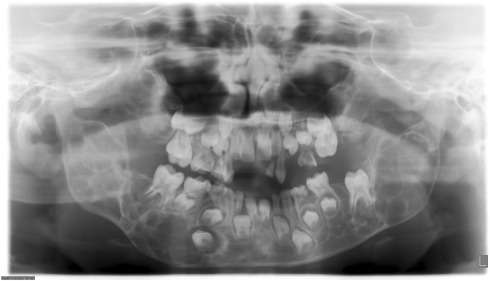

The morphology of the pulp chamber in primary molars can be evaluated using spiral computed tomography (SCT) (Selvakumar et al., 2014). SCT can provide information on the distance between the central fissure and furcation, the distance between the central fissure and the floor of the pulp chamber, the height of the pulp chamber, and the distance between the floor of the pulp chamber and the furcation (Selvakumar et al., 2014).